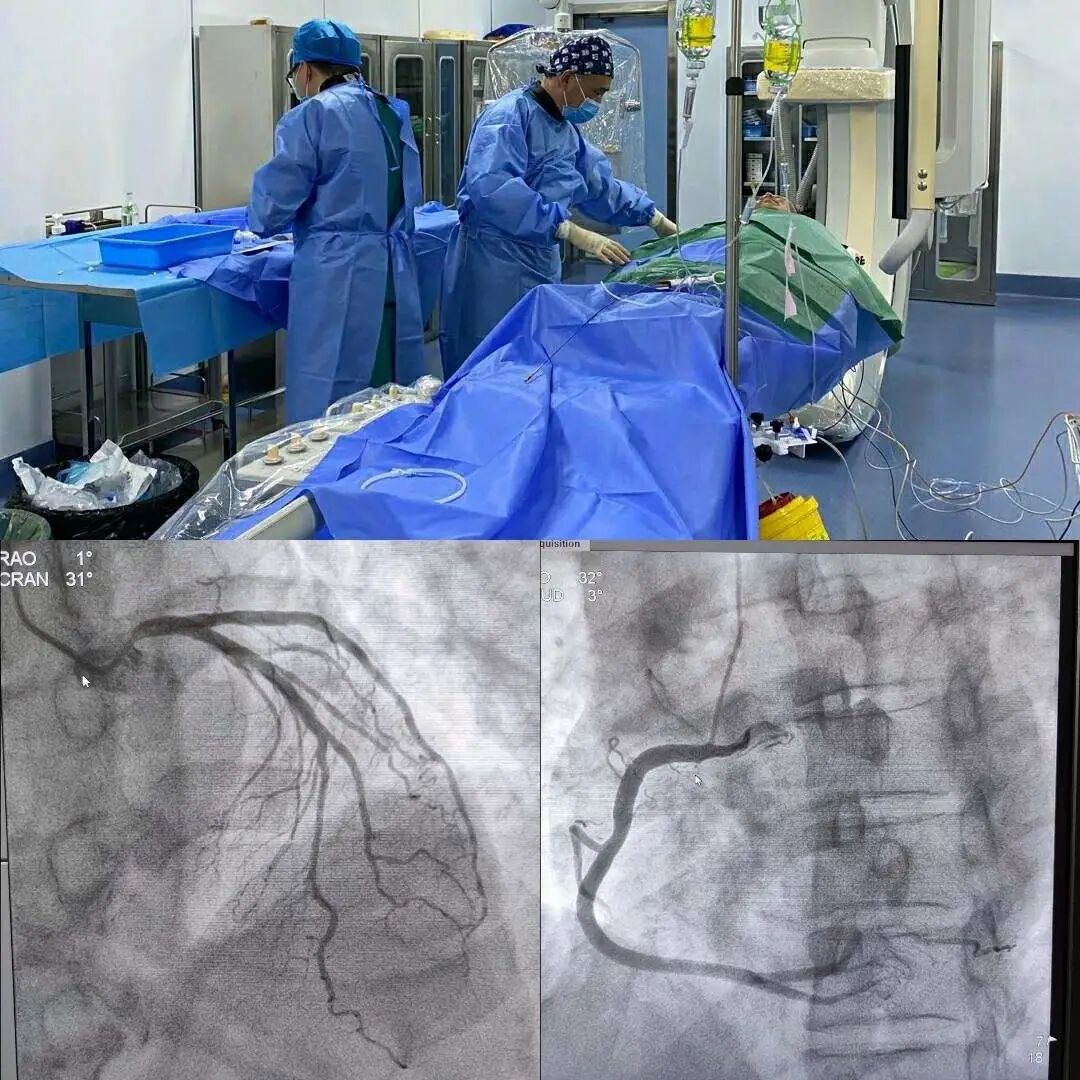

冠状动脉造影(coronary angiography)是一种有创性检查方法,通过在血管内插入导管,并注入造影剂,来观察冠状动脉是否存在狭窄、堵塞等问题。

它被视为诊断冠心病的“金标准”,能够直接显示冠脉的病变程度和位置,并且能够指导后续治疗方案的制定。

然而,冠脉造影需要住院检查,费用较高,属于有创性检查,因此在选择时需要慎重考虑。